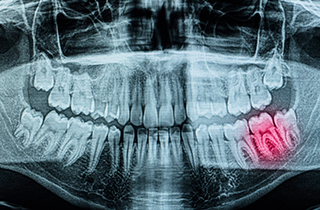

Various Diagnostic Methods for Dental Caries

After carefully evaluating the condition of a tooth affected by decay, we recommend the treatment that is best for the tooth.

• 02

Caries treatment for decay detected on X-ray imaging